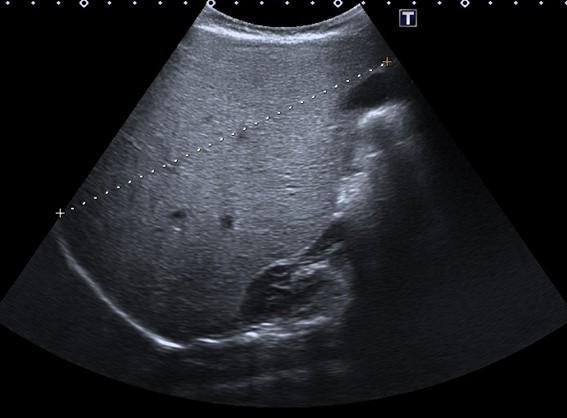

En la anamnesis, llama la atención la hiperfagia. Los padres refieren que come con mucho apetito y tiene hambre casi constantemente. También, la irritabilidad nocturna y la tendencia diaforética. En la exploración física, presenta aspecto macrosómico, con prominente panículo adiposo. Buena coloración de piel y mucosas, no ictericia. Abdomen distendido con hepatomegalia masiva de consistencia firme, hasta 12 cm bajo el reborde costal. No hay esplenomegalia. Exploración neurológica normal. En los análisis de sangre, presenta hipoglucemia (20 mg/dl) y elevación de transaminasas (GPT 289 U/l, GOT 550 U/l, GGT 125 U/l), hipertrigliceridemia (240 mg/dl) e hipercolesterolemia (280 mg/dl), creatin cinasa (CK) 89 U/l, lactato 1,3 mmol/l; con estudio de virus hepatotropos y autoinmunidad negativos. Estudio de coagulación normal. En la ecografía abdominal se visualiza una hepatomegalia masiva, con hiperecogenicidad difusa (Figs. 1 y 2). Ecocardiografía y exploración oftalmológica normales. Durante el ingreso, se llevan a cabo controles glucémicos, constatándose numerosas hipoglucemias de ayuno, todas ellas asintomáticas. Ante la sospecha de glucogenosis, se instaura tratamiento dietético con optimización de la ingesta de hidratos de carbono de absorción lenta, con lo que se consigue controles de glucemia normales previos al alta. Se realiza estudio metabólico sugerente de glucogenosis (oligosacáridos en orina: excreción elevada de hex4). En el estudio genético se objetiva variante patogénica c.556G>T(p.E186*) en el gen PHKG2 en aparente homocigosis, compatible con el diagnóstico de enfermedad de almacenamiento de glucógeno tipo 9C.

Figura 2. Eje anteroposterior del hígado (11,2 cm), también muy aumentado de tamaño para la edad de la menor, en un contexto de hiperecogenicidad difusa